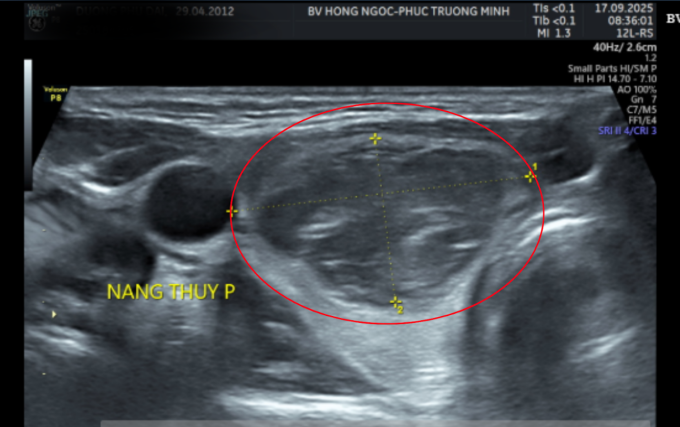

Kết quả siêu âm cho thấy khối u ở thùy phải tuyến giáp, kích thước hơn 3 cm. Sau chọc hút tế bào bằng kim nhỏ (FNA), bác sĩ nghi ngờ bệnh nhi mắc ung thư tuyến giáp thể nhú nhóm V theo phân loại Bethesda.